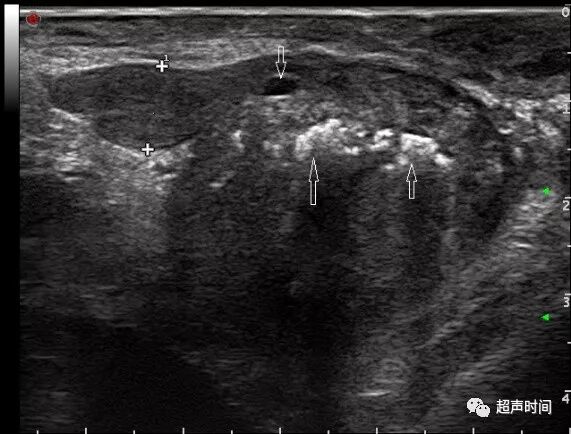

前列腺这一钙化带是内外腺的分界,也是外科包膜的标志。前列腺钙化表示良性增生(图 2),前列腺癌少有钙化。

图 2 前列腺增生伴钙化。前列腺体积 62 cm³,外科包膜多发钙化(箭头),外周带变薄,中央区和移行区增大,精囊腺厚 1.2 cm(测量标志)

病理性囊性变:局部组织缺血坏死液化所致,表现为囊性变,多见前列腺中-重度增生和癌变的组织内。囊变可单发,也可多个,形态不规则,位于病变组织内(图 4)。

图 4 患者 80 岁,前列腺体积 120 cm³,增生病变区小囊肿(箭头)